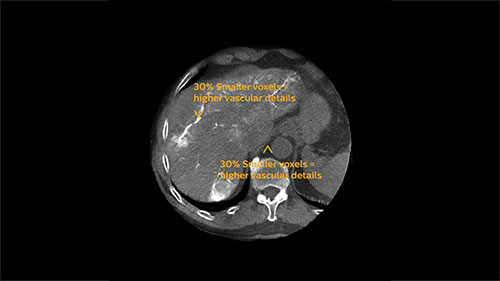

EmboGuide is based on XperCT Dual, a dedicated type of 3D oncologic imaging, which is used to visualize tumors and their feeding vessels.

XperCT Dual allows two phases of a contrast injection to be displayed next to each other. Clinicians can assess the feeder vessels to a tumor in the arterial phase and see the tumor boundaries in the delayed phase. Studies have shown that this novel method is superior to conventional DSA and provides equivalent imaging information to the gold standard of contrast enhanced MRI.³ ⁶

At the end of each procedure the dedicated oncologic imaging of XperCT Dual helps to determine the treatment endpoint in TACE for HCC.⁵ With XperCT Dual’s fast acquisition protocol, high resolution and soft-tissue contrast, a study has shown that its dual phase image information even correlates with the tumor response in the one-month follow-up MRI.